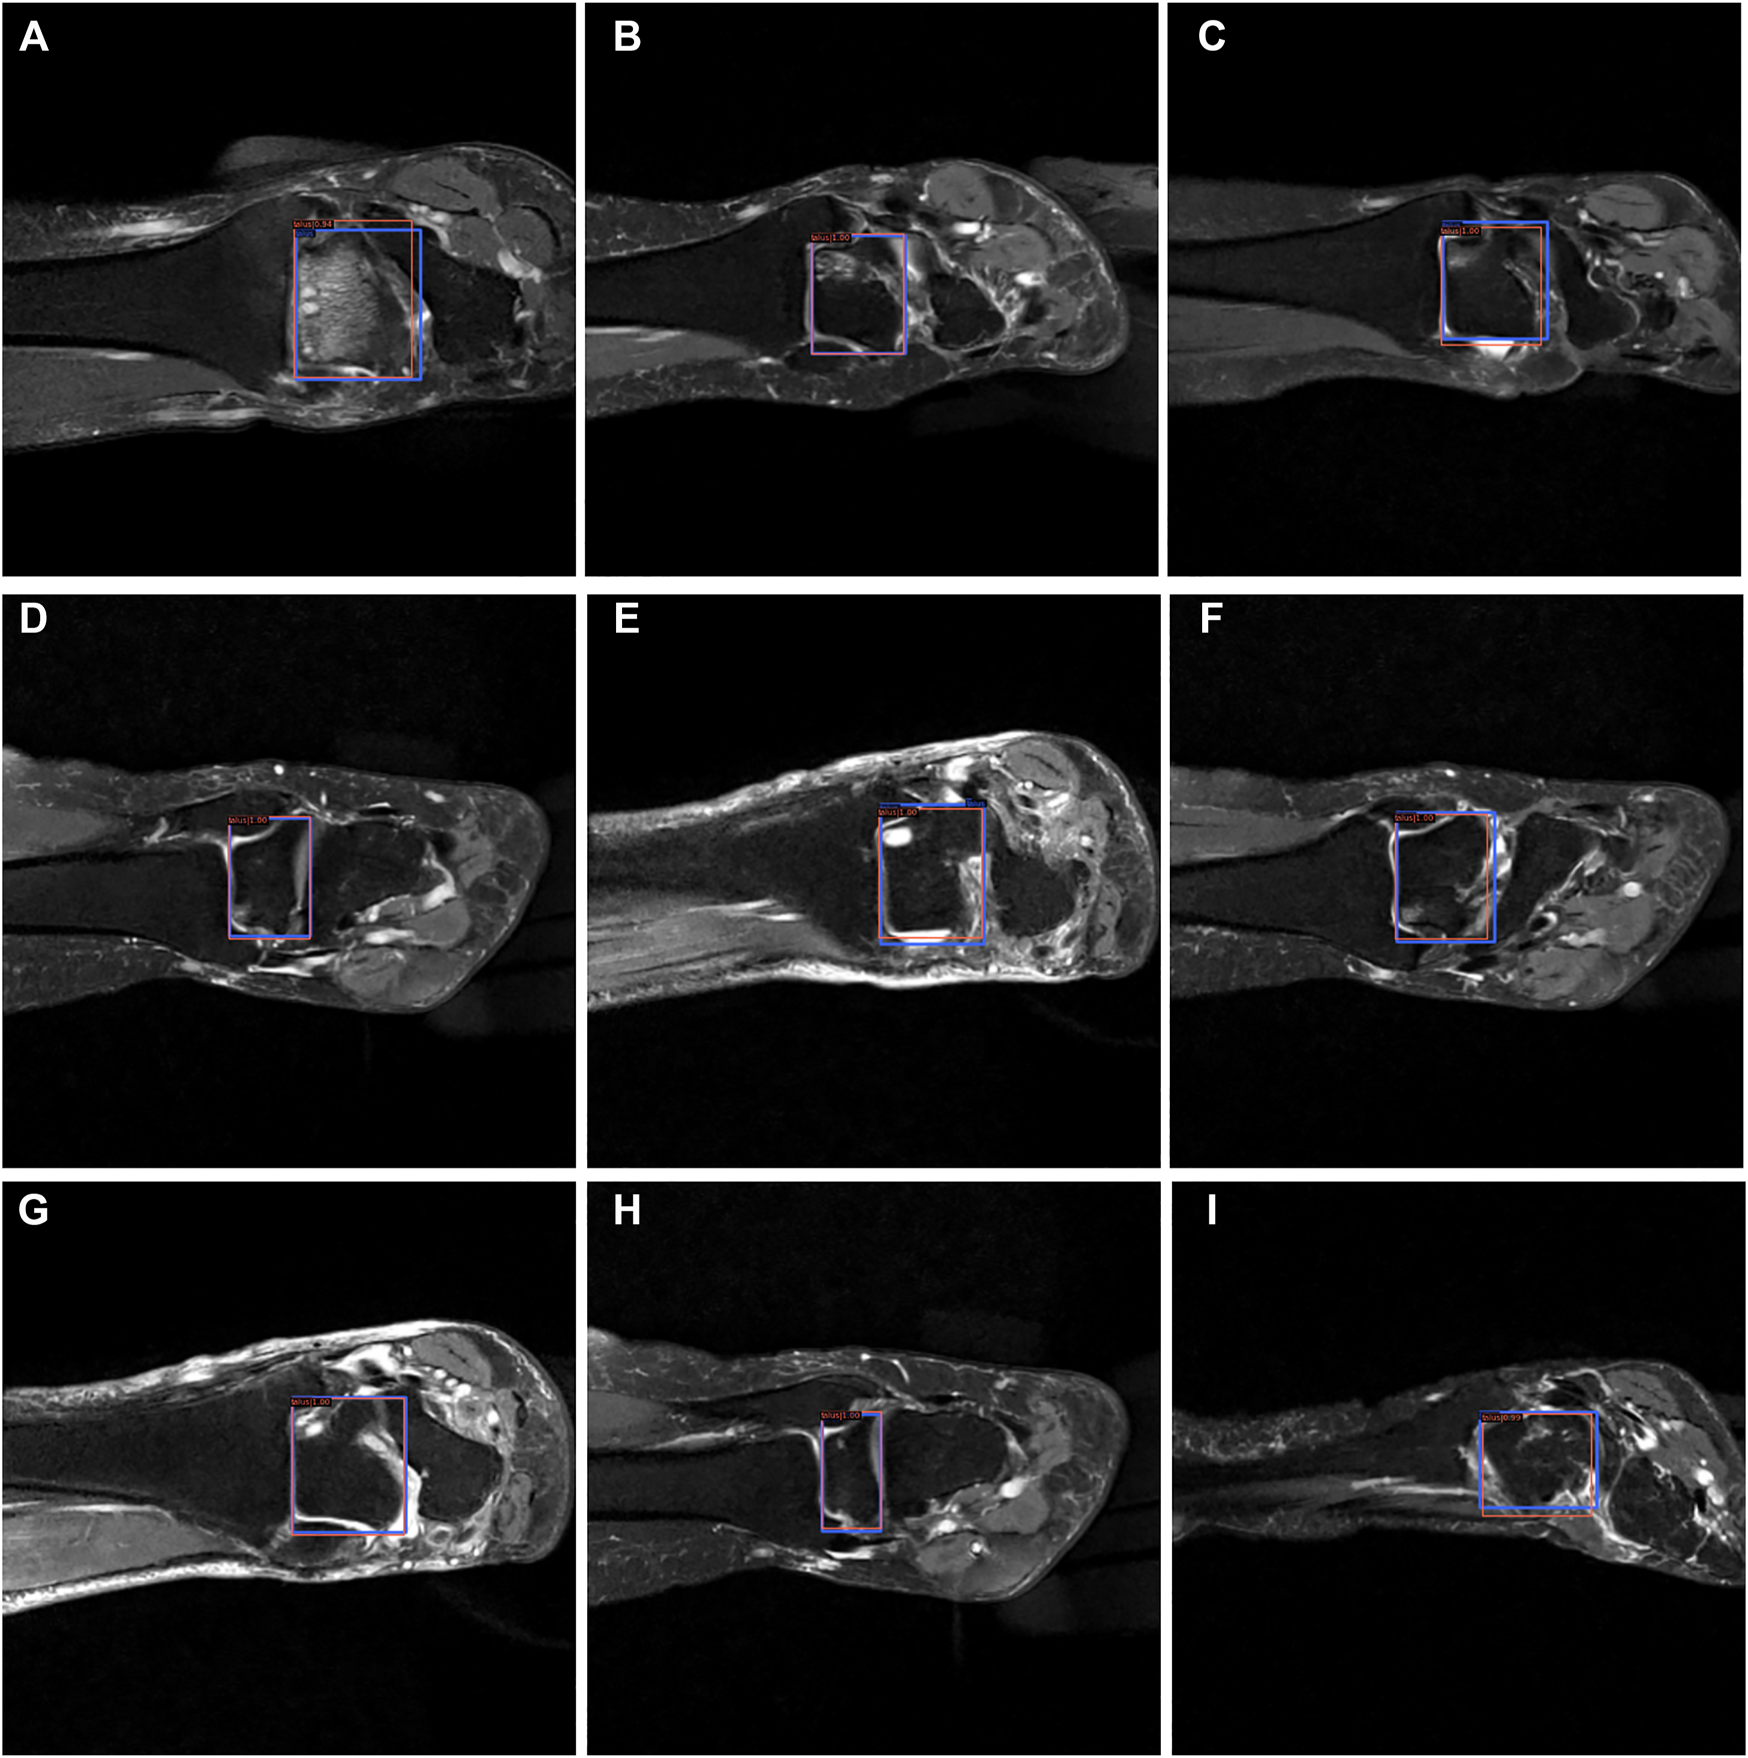

From Figures 7–9, we could intuitively observe that our network provided a comparable detection result (red bounding boxes) with that of senior radiologists (blue bounding boxes). Noticeably, our model achieved stable detection results on all three detection tasks, which shows the effectiveness of our method. More examples are shown in the Supplementary Figures S1–S3.

FIGURE 9

The bounding box visualization. Prediction result (red) vs. the ground truth (blue) of the talus itself. All the images (A–I) were selected from testing group to determine the AI recognition accuracy of talus itself. AI detection result was labeled by red rectangular. The ground truth was manually depicted and labeled by blue rectangular.